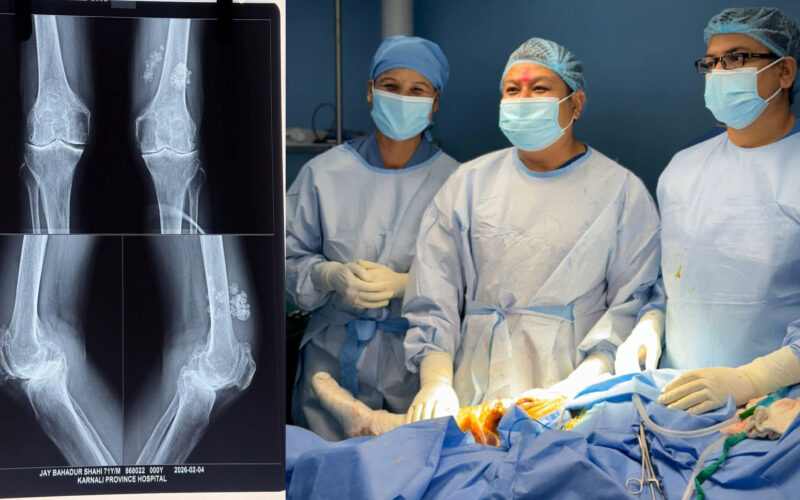

सफल भयाे ‘कृत्रिम घुँडा प्रत्यारोपण’